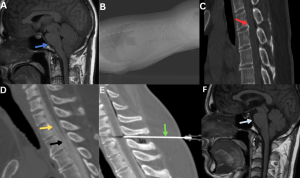

Fig 27: A patient presenting with orthostatic headache was diagnosed with spontaneous intracranial hypotension (SIH) secondary to a spinal CSF leak.

Figure A: Sagittal T1-weighted image of the brain shows sagging of the brainstem and descent of the cerebellar tonsils (blue arrow).

Figure B: Scout image showing the patient positioned in the decubitus position for the procedure.

Figure C: Sagittal CT image demonstrating a discogenic spur at the D1–D2 level (red arrow).

Figure D: CT myelogram demonstrating a dural tear (black arrow) with contrast tracking from the subarachnoid space into the anterior epidural space (yellow arrow) through the dural tear.

Figure E: Targeted epidural injection performed at the same level (green arrow).

Figure F: Post-epidural blood patch - Resolution of brain sagging on follow-up MRI (white arrow).